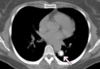

Imagen de TC de alta resolución que muestra fibrosis pulmonar.

Principales utilidades de TC de alta resolución son:

• Valorar el grado de afectación de enfermedades intersticiales pulmonares.

• En pacientes EPOC, para valorar el grado de enfisema y pequeñas zonas de atrapamiento aéreo.

• Determinar la gravedad y extensión de bronquiectasias.

• Valorar qué área es más rentable biopsiar.